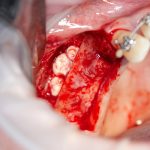

Кстати, обрати внимание на ширину альвеолярного гребня (левая картинка). Она чуть меньше 3 мм. Это объясняет, почему я засомневался в возможности установки имплантатов одновременно с остеопластикой. Понятно и без КЛКТ.

Наперво, мне нужно удалить разрушенный зуб и получить костный аутотрансплантат.